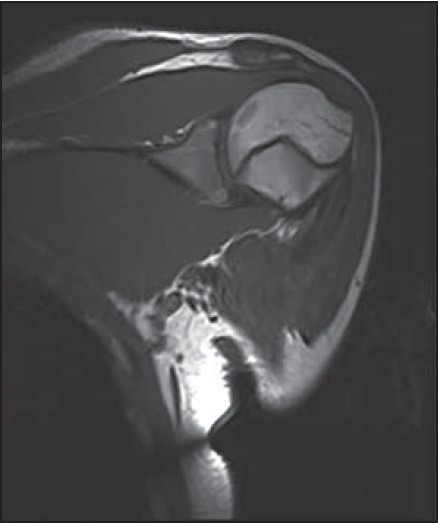

Initial X-ray and MR images were taken 3.5 months after the injury at an outside institution. The X-ray demonstrated an ossifying mass in the upper third of the arm within the pectoralis major muscle that coalesced with the underlying humerus [Figure 1]. The MRI showed some zoning phenomenon especially on the coronal T1 scan [Figure 2] and the water sensitive sequences also showed some swelling and high signal around the mass. A second series of imaging X-ray [Figure 3]a and b and CT scan [Figure 4] at 5 months showed further maturation especially of the outer compact bone of the mass with resolution of the surrounding soft tissue swelling at the insertion of the pectoralis major muscle. | Figure 1: AP X-ray of shoulder at 3.5 months showing an ossifying mass coalescing with the proximal humerus

| Figure 2: Coronal section MRI T1 at 3.5 months showing the zoning phenomenon

After a significant traumatic injury to a muscle, bleeding occurs into or around it. The resulting hematoma undergoes organization and mineralization from the outside in. This reflects the 'zoning phenomenon' characteristically seen with myositis ossificans in which three distinct zones have been classified. [1] The central zone is made up of fibroblasts and necrotic muscle; the middle zone has osteoblasts and immature bone and the most peripheral zone is formed of mature trabeculoid distinct from the surrounding tissue. This shows on films as a well-circumscribed mass with an outer layer of ossification and a lucent centre. Depending on the level of maturation of the lesion, all three zones might not always be clearly demonstrated radiographically. Calcification of the lesion is seen as early as 11 days up to 4 weeks. Ossification and formation of a sharp circumscribed mass occur at 4-8 weeks, and the lesion reaches full maturity after 5 months. [1]

Standard radiographs often appear normal during the early stages of myositis ossificans but can show de novo pathognomonic ossification surrounding a clear central area at a later stage. [2] Some reports suggest ultrasound to be the most sensitive imaging modality to detect early zone phenomenon in myositis ossificans. [15] MRI may show the so-called zone phenomenon even before the ossification appears. CT scans are more sensitive than radiography for detecting ossification and may also show a central fatty metaplastic area. [16]